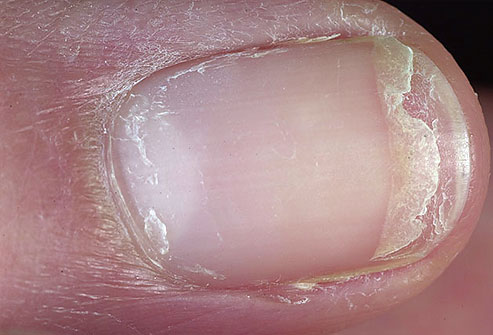

Unha rachada no meio? Pode confessar, esse detalhe incomoda e ninguém quer que percebam. Mas calma, a gente te mostra como resolver isso de vez!

Por que sua unha está abrindo no meio e o que isso diz sobre sua saúde

Vamos combinar, a unha rachada no meio é um problemão que vai muito além da estética. Geralmente, ela é um sinal de que algo não vai bem, e entender a causa é o primeiro passo para dar um basta nisso.

Em Destaque 2026: Uma unha rachada no meio pode ser resultado de impacto ou sinalizar unhas fracas, necessitando de cuidados. Rachaduras profundas ou recorrentes indicam a necessidade de investigar a causa raiz.

Unha Rachada no Meio: O Que É e Por Que Você Precisa Dar Atenção AGORA!

Vamos combinar, poucas coisas são mais frustrantes do que aquela unha rachada no meio, né? A gente tenta disfarçar, passa esmalte, mas a verdade é que ela sempre dá um jeito de aparecer, estragando qualquer visual e, sejamos francos, incomodando demais. Não é só uma questão estética; essa rachadura pode ser o grito de socorro das suas unhas.

Pode confessar: você já deve ter pensado que é só falta de cálcio ou alguma coisa boba. Mas preste atenção: a unha rachada no meio, seja na mão ou no pé, esconde detalhes importantes sobre sua saúde e seus hábitos. É o tipo de sinal que, se ignorado, pode virar um problema bem maior do que um simples \”descuidinho\”.

Onicopapiloma: Este é um caso mais específico e que merece total atenção. Uma rachadura vertical persistente, muitas vezes acompanhada de uma linha colorida (avermelhada ou marrom) ao longo da unha, pode indicar a presença de um onicopapiloma. É um tumor benigno, mas que necessita de avaliação dermatológica para um diagnóstico preciso e, se for o caso, tratamento adequado.